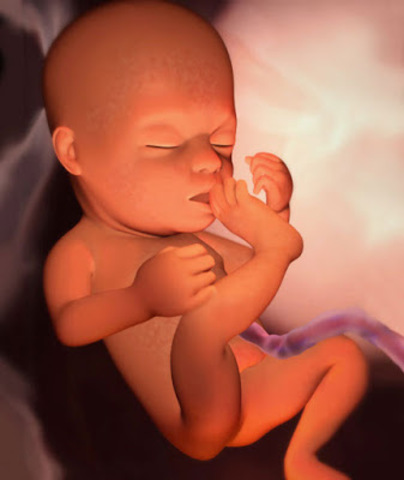

• SEMANA 40

SEMANA 40

Solo un 5% de los bebés nace en día exacto previsto, el parto puede demorar un par de días más, o adelantarse de igual forma.

SEMANA 39

Ahora todo su cuerpo está listo para nacer y enfrentar al nuevo mundo que le demandará nuevos esfuerzos a los que hasta hoy no está acostumbrado.